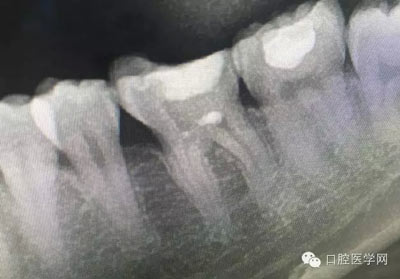

深齲或者是齲壞備洞的時候意外穿髓,我們怎么處理好些?后期出現(xiàn)的牙髓的癥狀,是我們操作的問題?比如細菌層的存在,我們沒有清理干凈?還是我們窩洞沒有進行消毒,或者是隔濕沒有做好導致的粘結出現(xiàn)問題,還是材料充填的時手法不對,導致的材料收縮過大,還是我們的光照設備出現(xiàn)了老化沒有完全達到想要的固化,還是懸空的釉質沒有去除導致的微滲漏的發(fā)生,或者是材料本身對牙髓產生的刺激,還是材料選擇的問題,或者是我們對材料的性能和說明沒有足夠的了解導致的,沒有按照材料的要求去做,還是我們自身對牙齒情況的判斷出現(xiàn)的問題......